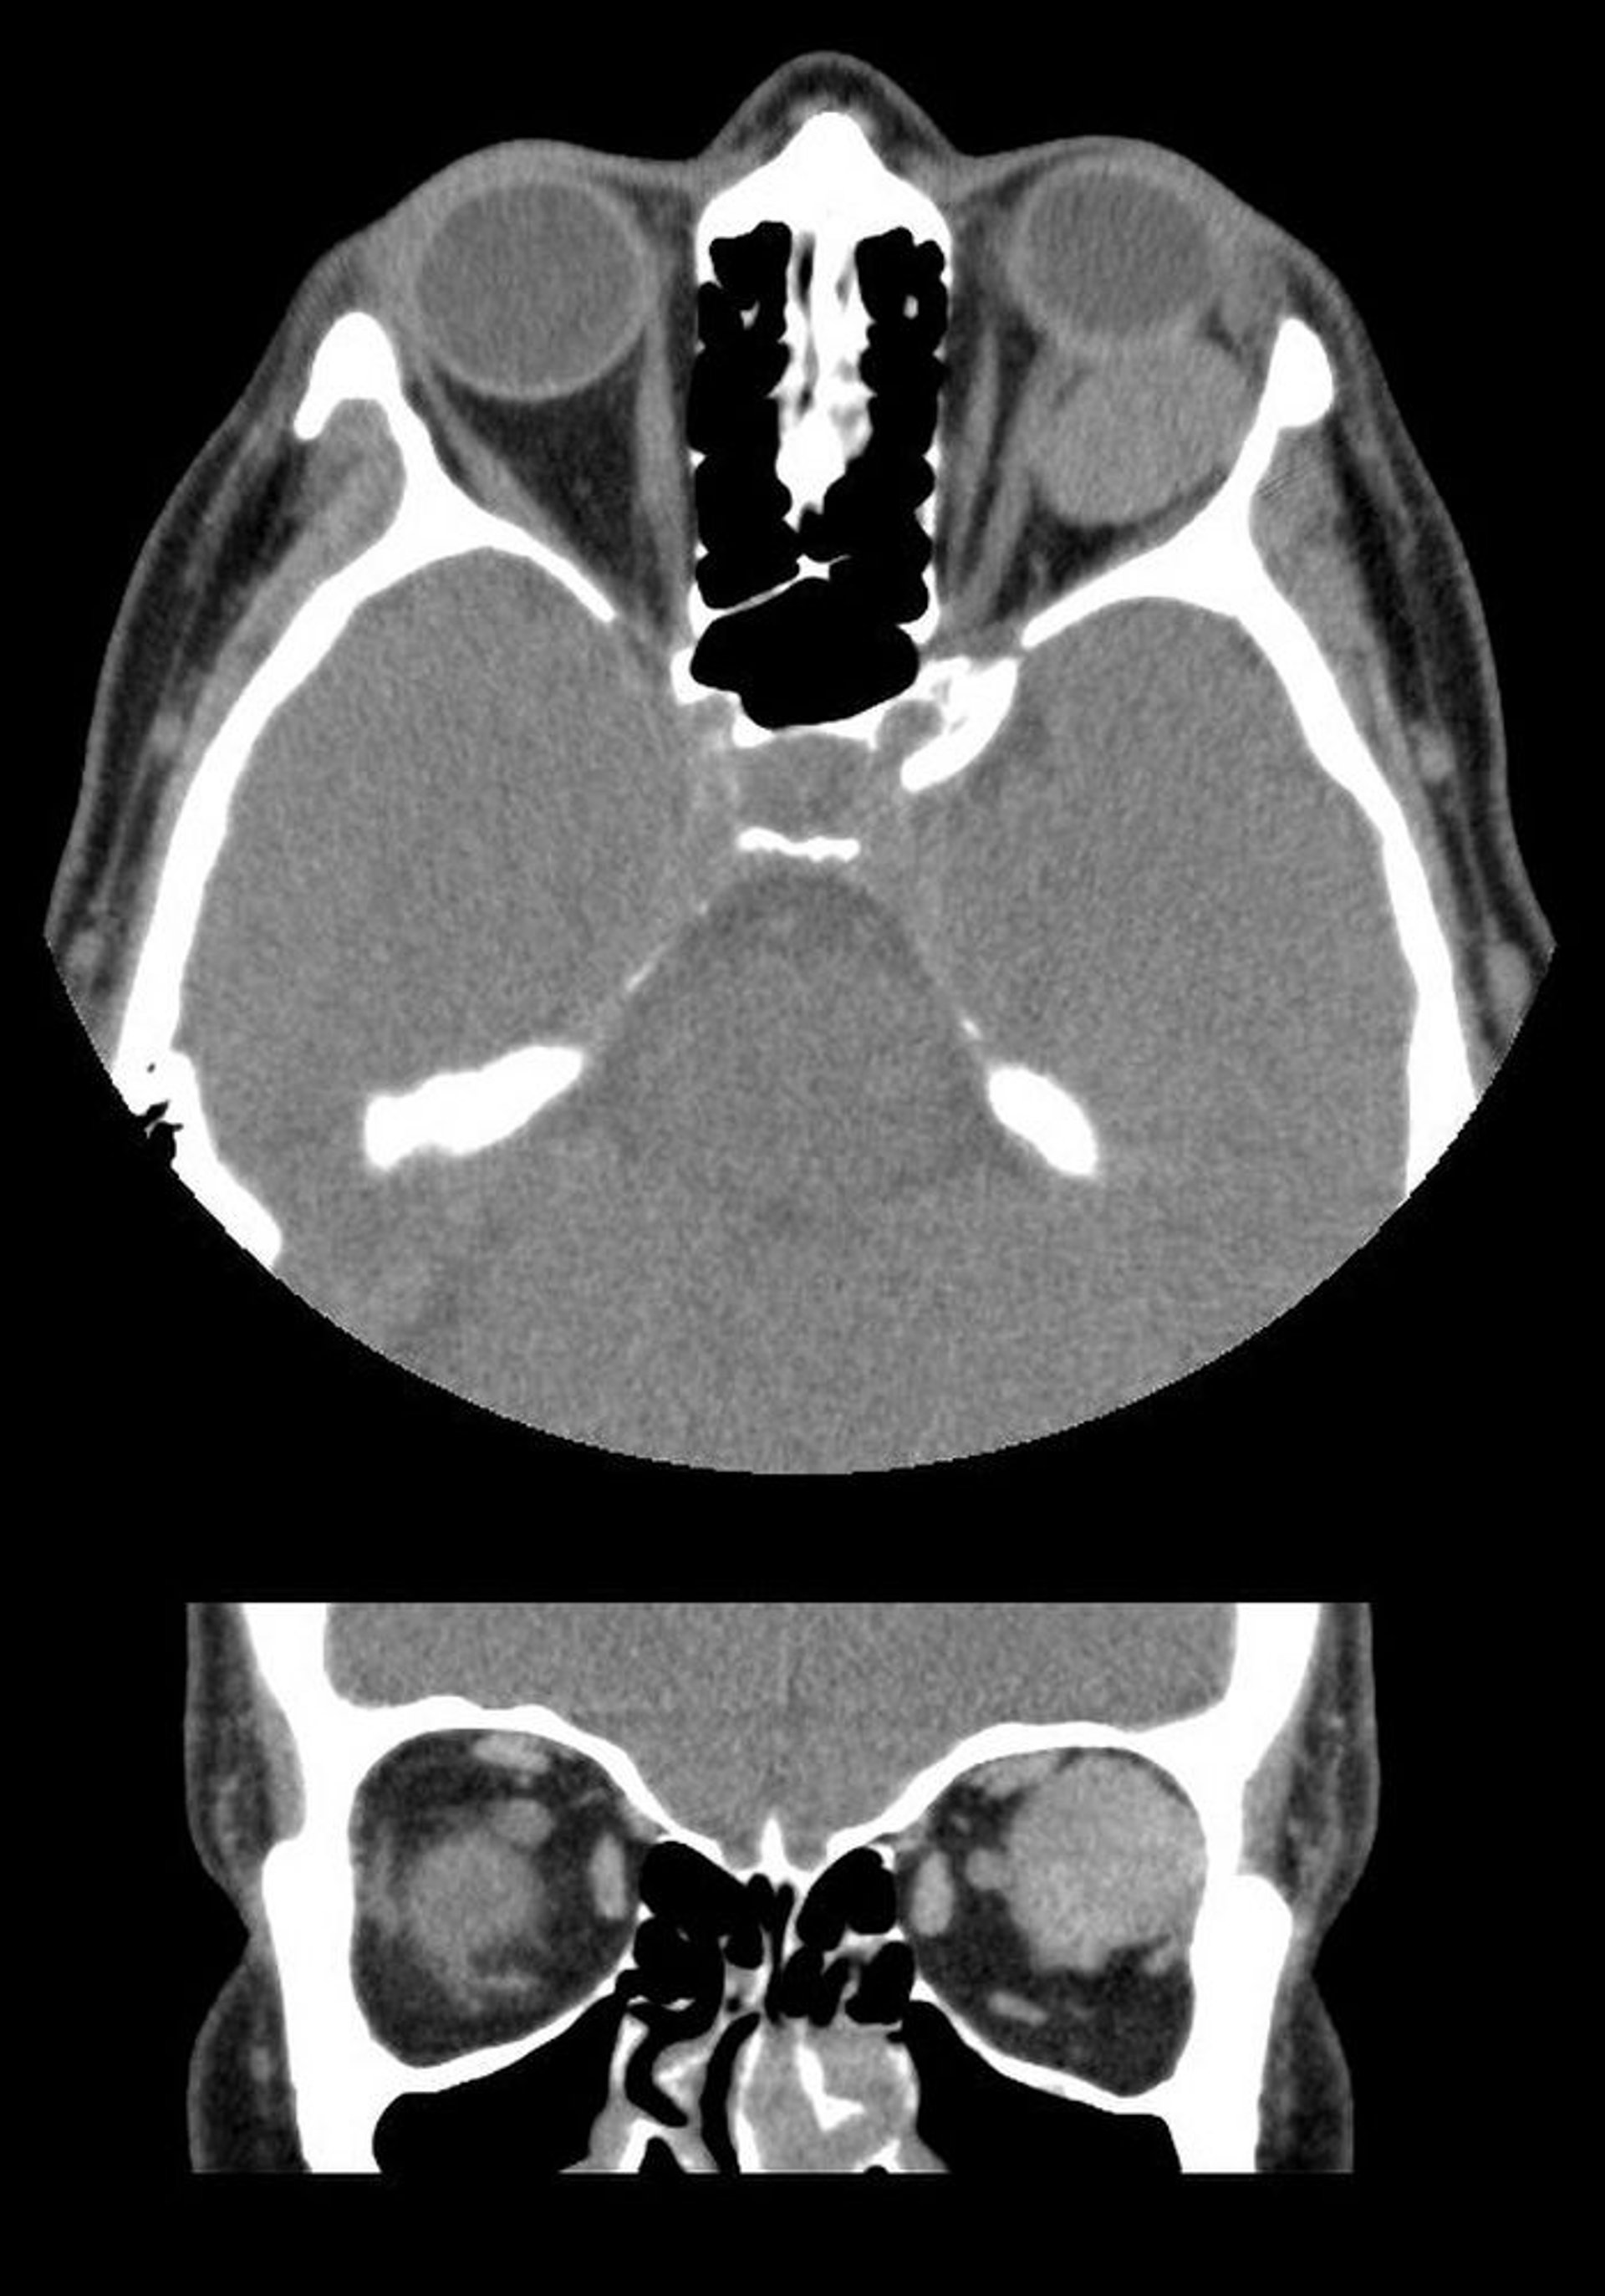

Emangioma cavernoso

In questa immagine, le TC assiale (in alto) e coronale (in basso) mostrano una massa intraconale ben demarcata dietro il globo oculare sinistro. La massa è una malformazione venosa cavernosa.

Images courtesy of James Garrity, MD.